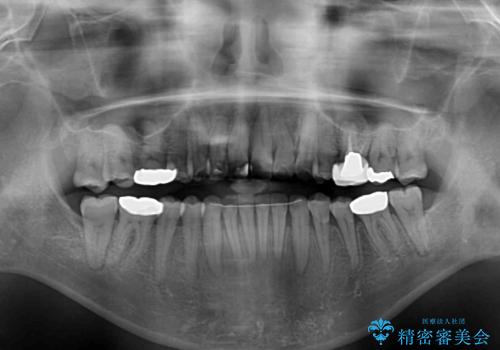

舌のトレーニングをしっかりと行ってくださり、10ヶ月で希望通りの歯列となりました。

日頃から飲まれる飲み物の影響で着色しやすいため、来院の度に着色除去のクリーニングも行っていました。